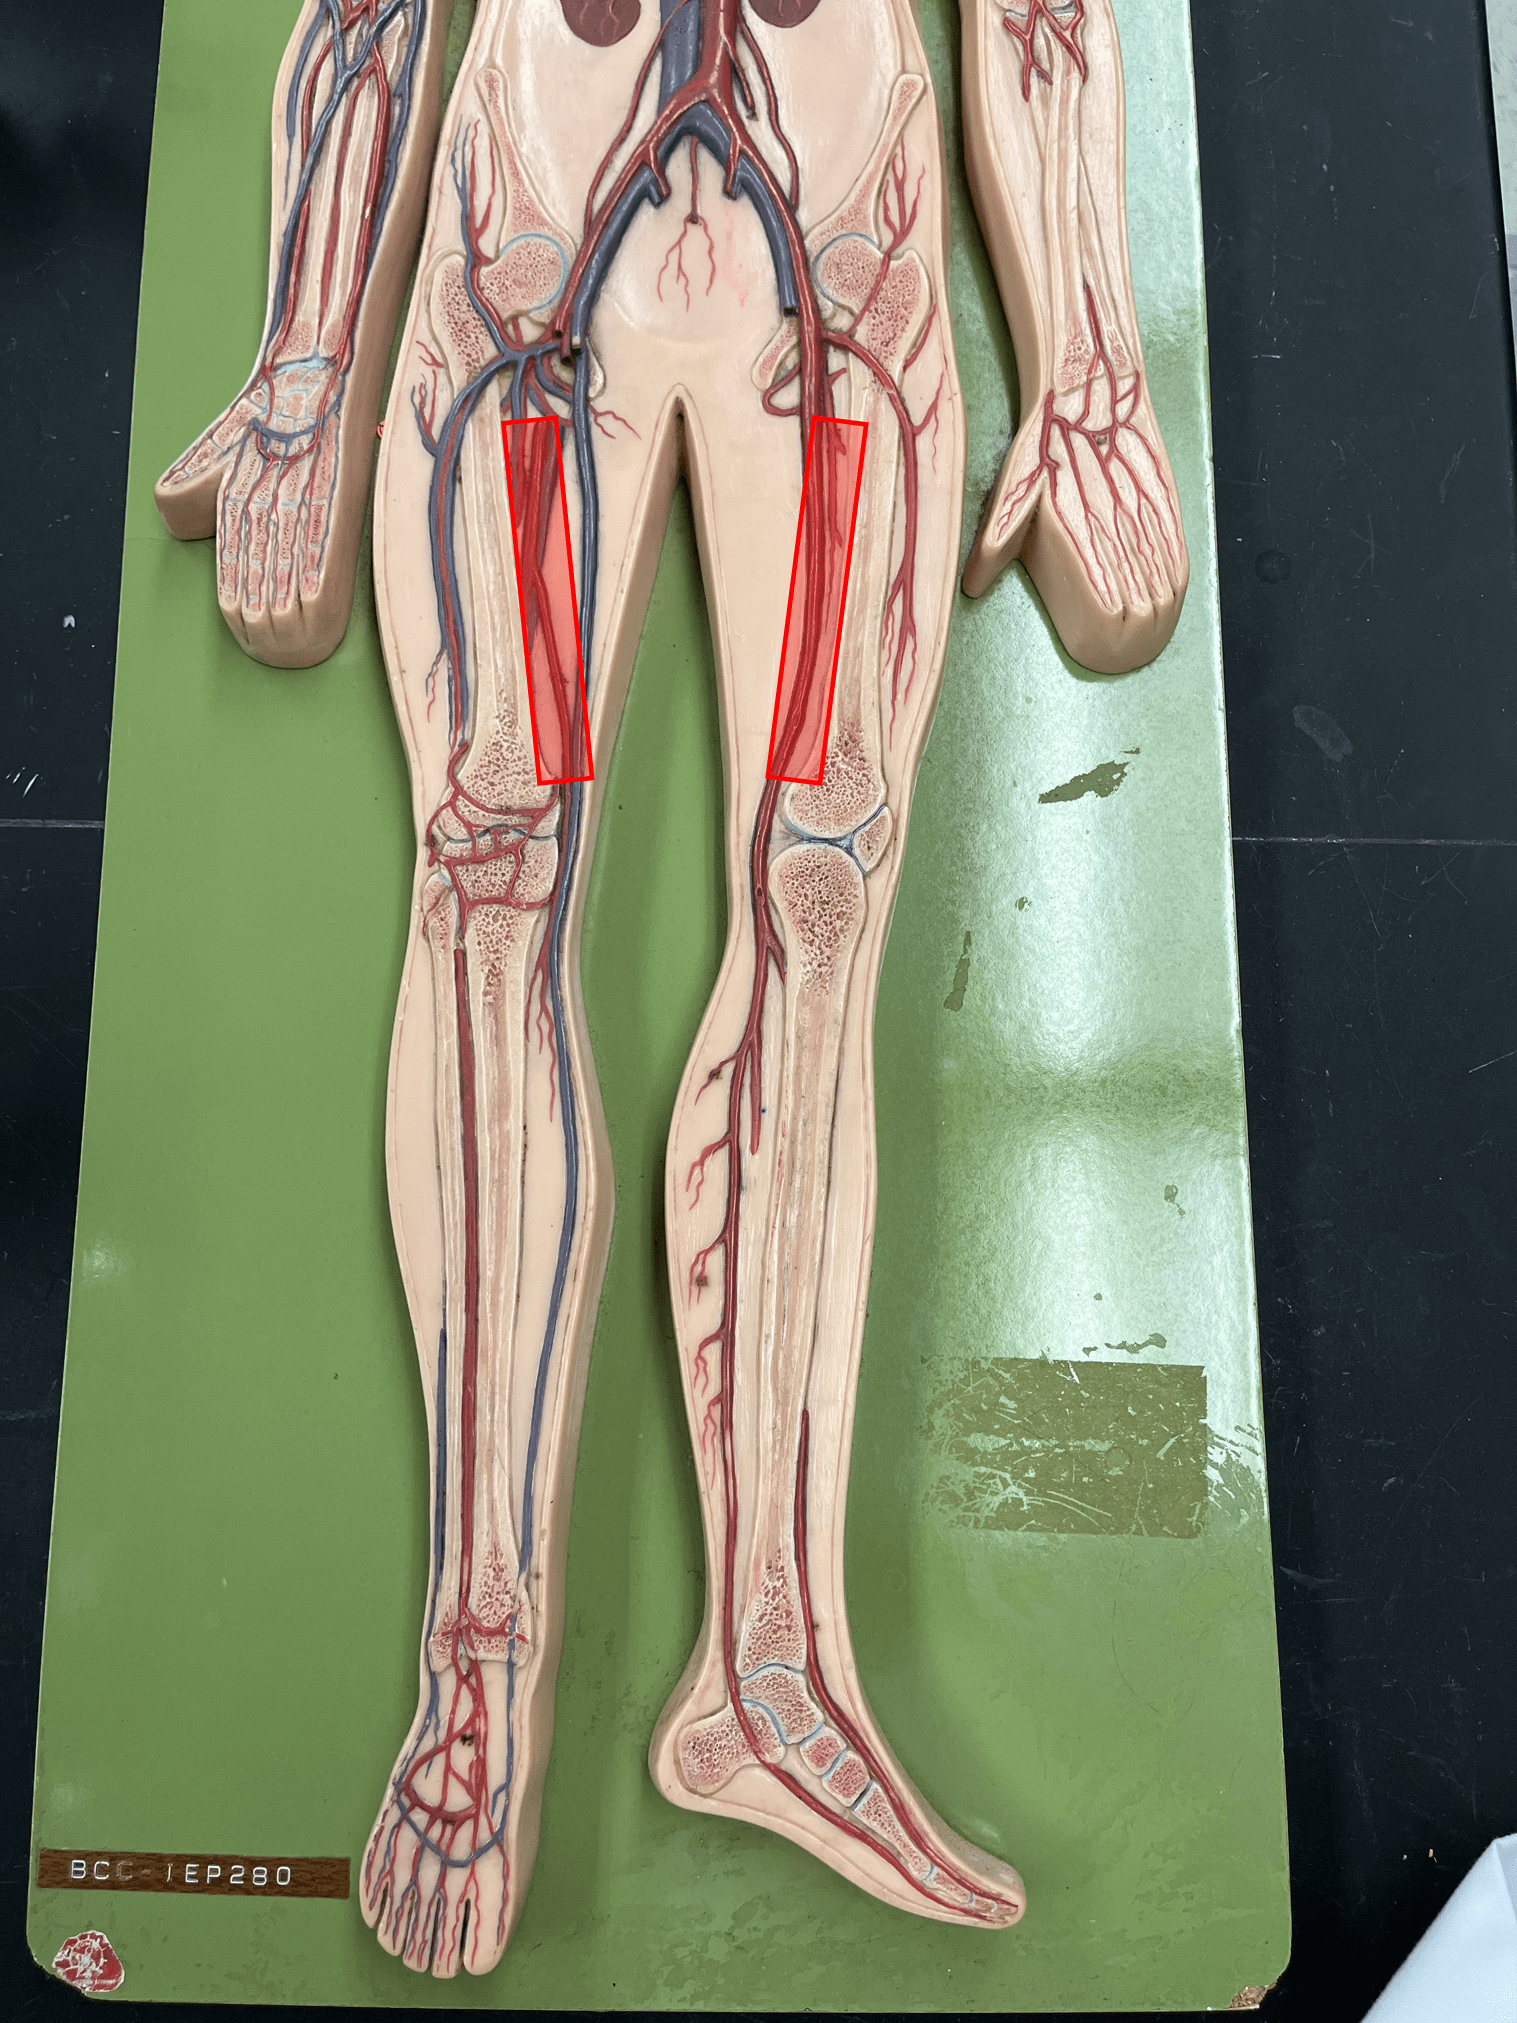

endothelium

• Part of the tunica interna.